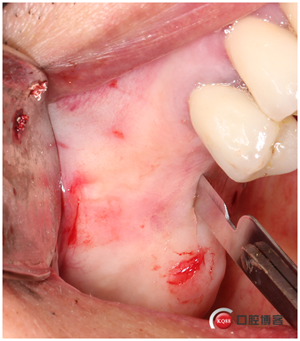

修整牙槽嵴頂,切記從這時(shí)候開(kāi)始所有取下來(lái)的骨頭都是寶貝。

下頜就是常規(guī)種植,主要看的還是上頜外提升。咱可要一步步仔細(xì)看好了,看看我這種方法做外提升快不快、安全不安全?

1mm停止環(huán)安裝到開(kāi)孔鉆上,在要開(kāi)窗的部位中心位點(diǎn)用800-2000轉(zhuǎn)的速度打孔。